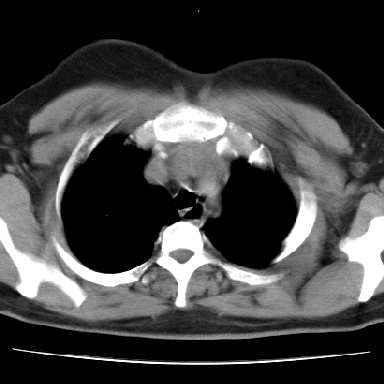

f 37 咳嗽1周,咯血1次,无浓痰,无明显发热

左下肺肿块影,内可以见小泡征,并见厚壁空洞形成,洞内缘凹凸不平,可见壁结节。靠近胸膜侧可见胸膜凹陷征。左侧胸腔内可见少量低密度积液影。右肺可见两处高致密的小结节影。

考虑:左下肺周围型肺癌伴右肺转移